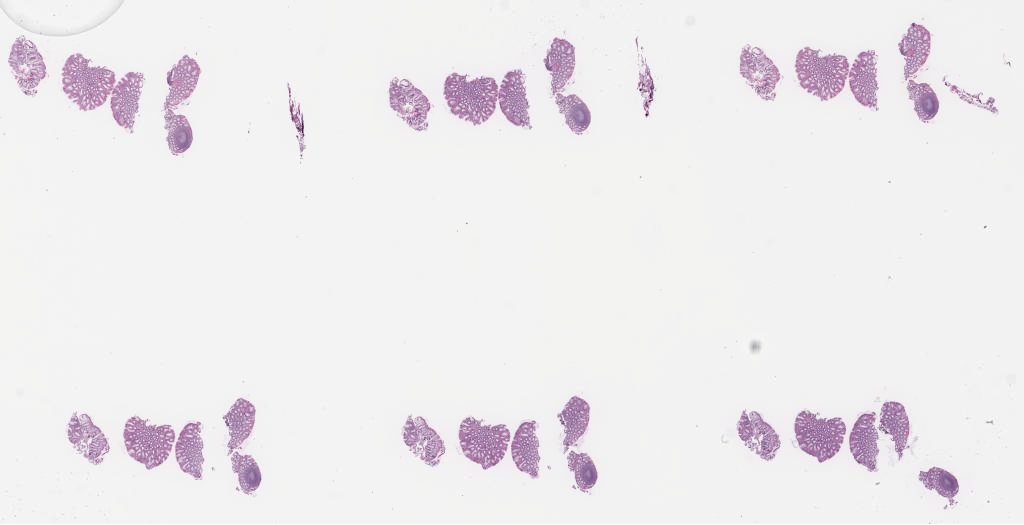

Case1 2a.svs

153384

x

78544

40X